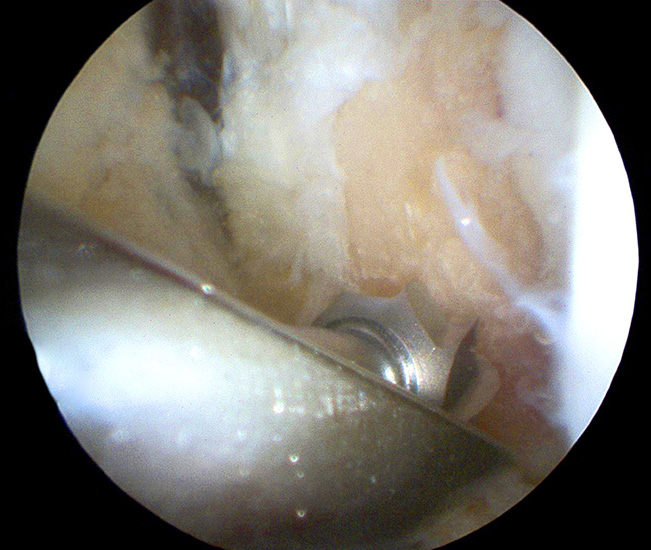

Operationstechnik

Nachfolgend wird die OP-Technik an einem rechten Sprunggelenk unter Verwendung von PEEK-Ankern veranschaulicht.

- Ausreißen/Fehlpositionierung der Nahtanker: Um eine Fehlpositionierung der Anker zur vermieden, sollte die distale Fibula sorgfältig dargestellt werden, so dass die distale Spitze eindeutig identifiziert werden kann. Es hat sich als günstig erwiesen, zuerst den distalen Bohrkanal bzw. Fadenanker zu positionieren und zu überprüfen, ob dieser vollständig knöchern platziert ist. Aufgrund der spitz zulaufenden und abgerundeten Anatomie der Fibulaspitze besteht das Risiko, dass bei einer Positionierung zu weit distal kein ausreichendes Knochenlager gegeben ist. Ggf. kann eine Korrektur durch eine Neupositionierung weiter proximal durchgeführt werden. Diese Korrekturmöglichkeiten können unter Umständen eingeschränkt sein, wenn sich der proximale Anker bereits in situ befindet. Darüber hinaus muss bei der Anlage der Bohrkanäle bzw. beim Einbringen der Anker auf die korrekte Zielrichtung in der Sagittal- und Transversalebene orthograd zur Fibulaschaftachse geachtet werden. Eine Schräglage des Ankers kann dazu führen, dass das Implantat nicht vollständig im Knochen zu liegen kommt und mechanische Irritationen am lateralen Talus verursachen. Ist das Implantat nicht regelrecht im Knochen verankert, begünstigt dies ein Ausreißen oder Ausbrechen des Ankers. Letzteres kann in einer Fraktur des Außenknöchels resultieren.